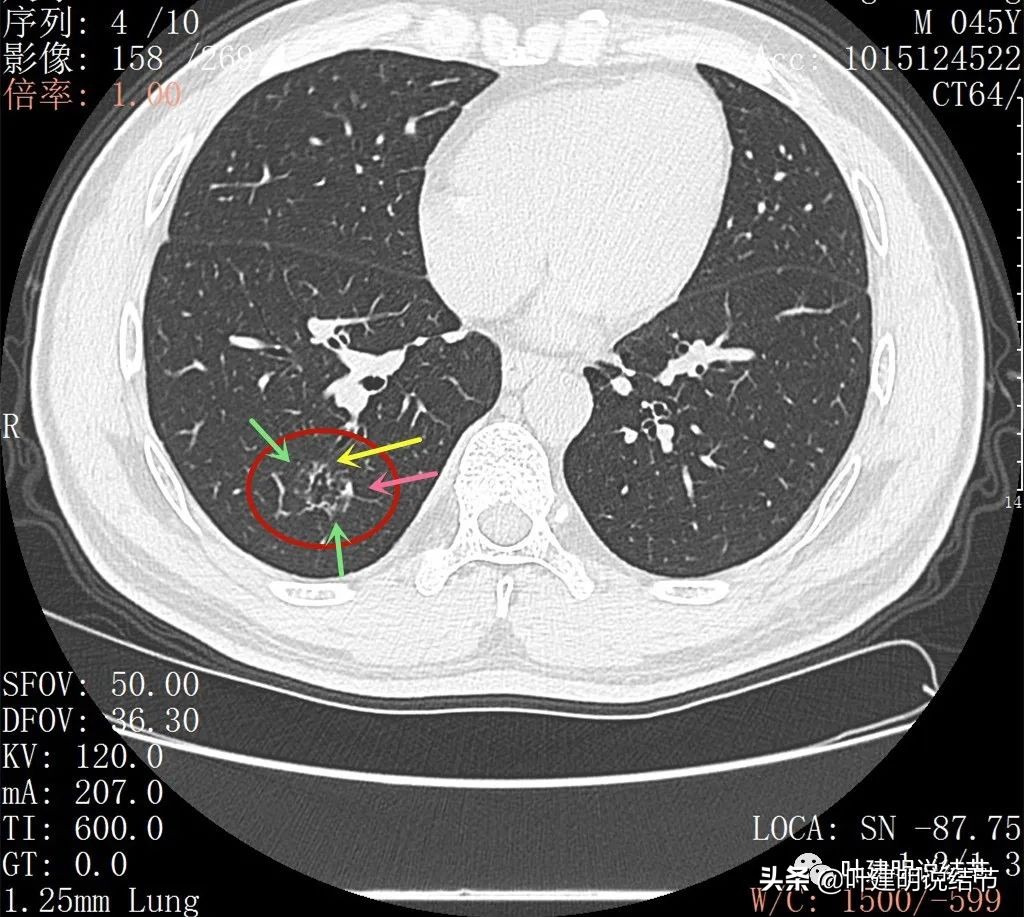

再来看薄层扫描:

病灶感觉很散在,但内部有扩张的细支气管(黄色箭头)、边缘略显不清(绿色箭头),部分有偏实性(粉色箭头)。

边缘血管异常增粗(桔色箭头),边缘显糊(绿色箭头),细支气管扩张(黄色箭头)

病灶似乎非圆形或类圆形,扩张的细支气管壁密度偏高(蓝色箭头),感觉比较僵硬(黄色箭头),病灶轮廓显模糊(黄色箭头)

扩张细支气管壁密度较高,病灶轮廓显糊